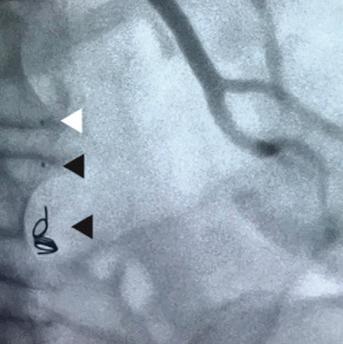

IMPEDE® Embolization Plug GENERATES NEW HEALING POSSIBILITIES CONFORMS TO THE ANATOMY UNPARALLELED VOLUME RETURNS

Supports thrombus formation throughout porous scaffold Reshaping your view of clinical success through the science of smart polymer LIT1095 Rev A IMPEDE® Embolization Plug IMPEDE-FX Embolization Plug www.shapemem.com Smart

Radiolucent smart polymer © 2022 Shape Memory Medical Inc. All rights reserved. 807 Aldo Avenue, Suite 109, Santa Clara, CA 95054 USA +1.408.649.5175 | info@shapemem.com | www.shapemem.com Indications: The IMPEDE Embolization Plug is indicated to obstruct or reduce the rate of blood flow in the peripheral vasculature. The IMPEDE-FX Embolization Plug is indicated for use with the IMPEDE Embolization Plug to obstruct or reduce the rate of blood flow in the peripheral vasculature. Refer to the IFU – supplied with each device – for a complete statement of the indications, contraindications, warnings, and instructions for use. Inferior Mesenteric (IMA) and Renal Accessory Artery angiographic image courtesy of Alexander Maβmann, MD, Saarland University Medical Center, Homburg/Saar, Germany. The images are illustrative and do not represent the actual size of any products. Patent: www.shapemem.com/patents Shape Memory Medical products and associated components are not available in all countries or regions. Please contact your Shape Memory Medical representative for details regarding product availability. Shape Memory Medical and IMPEDE are registered trademarks of Shape Memory Medical.

IMPEDE-FX Embolization Plug